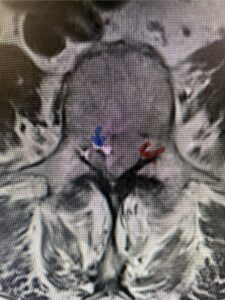

The next patient is a 56-year-old morbidly obese female who had progressive leg pain and weakness. She was over 320 lbs and did not have diabetes either. On MRI she had a massive disc herniation spanning the L3-4 and L-4 interspaces, centered behind the L4 vertebral body (Fig 3A and B). She also had an L4-5 spondylolisthesis. There were opinions that the disc emanated from the L3-4 disc space, but because of spondylolisthesis and on careful inspection of the MRI, there was a high chance the disc herniation had instead emanated from L4-5 (Fig 4). She had conservative treatment including epidurals but had worsening strength and numbness. She was scheduled electively for surgery, but then fell, and broke her ankle. She could not walk, particularly due to the pain down her leg. She was taken to the operating room urgently after she was cleared medically. She had no issues cardiologically and was taken to the operating room. The patient underwent a laminectomy that extended above the L3-4 disc space to below the L4-5 disc space. We encountered mainly centered on the left at the level of the L4 vertebral body and massive disc herniation that created a huge cavity in the lumbar canal. It was covered in an interesting thin membrane that we dissected off the disc herniation (Fig 5). Postoperatively the patient did experience significant relief of pain, but some improvement of strength. In combination with the ankle fracture and the extent of preoperative weakness, the patient required extensive rehab. The patient also developed a seroma and some wound drainage issues that were treated locally.

Fig. 3a : Sagittal T2-weighted lumbar MRI demonstrating a massive L4-5 disc herniation with superior migration behind the L4 vertebral body and taking up most of the left side of the spinal canal (red arrow) Note the slight grade one spondylothesis at L4-5 (blue dash). Notice the severe compression of the thecal sac (blue arrow) by the large left sided disc herniation (red arrow)

Fig. 3b: Axial T2-weighted lumbar MRI demonstrating severe compression of the thecal sac (blue arrow) by the large left sided disc herniation (red arrow) taking up most of the left side of the spinal canal (red arrow)